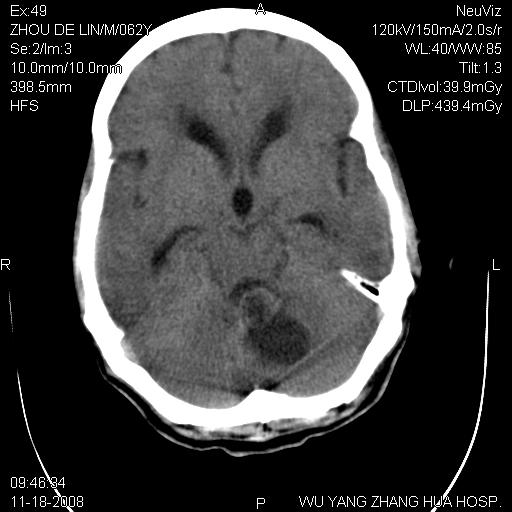

患者近段时间偶有头晕,无其他不适。既往有糖尿病病史。

小脑中线区见一类圆形混杂密度影,四脑室受压变形,其后方见一边界清楚的囊性低密度影,幕上脑室扩张。小脑中线区肿瘤,儿童多见于髓母细胞瘤,成人多见于胶质瘤。

诊断:小脑胶质瘤可能性大。建议增强扫描

小脑囊实性占位病变、脑室系统积水扩张、脑肿胀。

小脑囊实性占位病变、脑室系统积水扩张,建议增强

患者4个月前在外地曾做ct<。与本片对比无明显变化(未治疗)。曾在外院做mr,病人未带来,嘱家属改天带来再上传给老师们看看。

1)小脑蚓部(偏左侧)占位性病变;不排除转移瘤可能。建议行进一步检查。2)脑积水。

脑积水。小脑蚓部占位性病变不排除转移瘤可能。